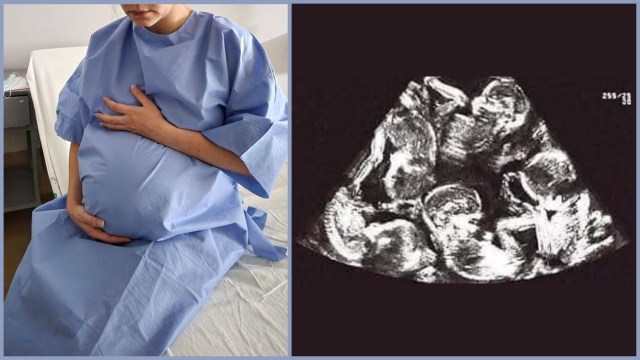

¡Ni a uno, ni a dos, sino a trece bebés! En Ixtapaluca, Estado de México, un bombero y su esposa se encuentran en la espera de un embarazo múltiple de trece bebés, un extraño pero […]